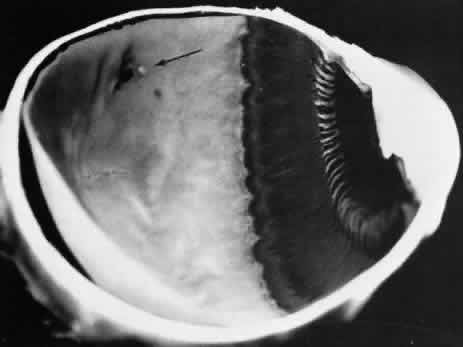

The zonular-traction retinal tuft always projects from the retinal surface internally and anteriorly toward the zonule (Fig. 40). Usually single and located within the vitreous base, zonular-traction retinal tufts are joined to zonular fibers at the apex; the tufts, which vary in length and thickness, are associated with a broad range of trophic and tractional alterations at the retinal end of the process. Histopathologic changes include zonular attachments at the apex, neuroglial cells within the tuft, and degeneration with retinal thinning at the base (Fig. 41). Retinal holes and tears result from the combination of trophic changes at the base and traction resulting from zonular fibers. Within the vitreous base and posterior to it, zonular-traction tufts may be associated with partial-thickness or full-thickness retinal tears that can occur in the absence of posterior vitreous detachment.

Fig. 40. Zonular-traction tuft of the peripheral retina. Tuft is drawn at an acute angle from the retinal surface toward the ciliary body and shows microcystic degeneration anteriorly. Posteriorly, the tuft splays; the retina at its base shows marked trophic change, including three full-thickness holes (arrow). (× 20.)